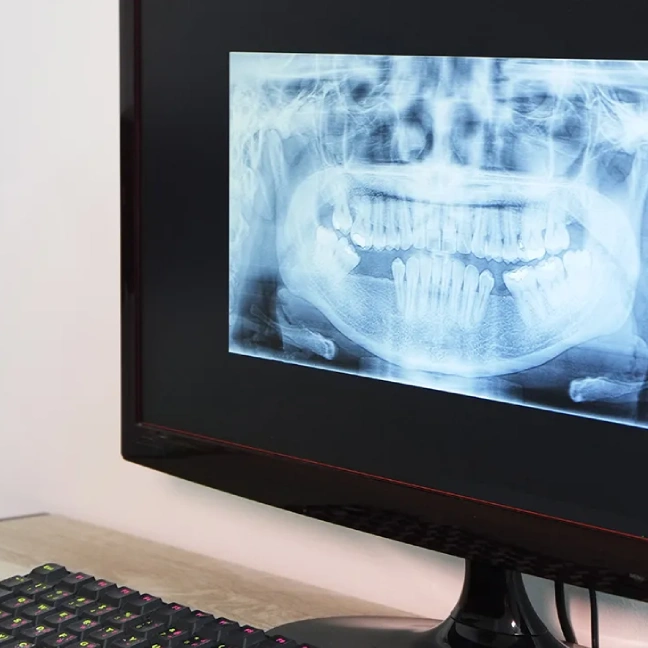

Digital X-Rays

in Plantation

Digital x-rays are safe, quick, and comfortable. Using the latest technology, we can create crisp, high-resolution images of your mouth’s structure, so we can make accurate diagnoses and treatment plans. Digital x-rays use only a fraction of the radiation as traditional film x-rays, so you can rest easy. Most patients receive one or two full sets of x-rays every year, but we may recommend additional imaging in the case of a dental emergency, or if we find an oral health issue that we need to investigate further.